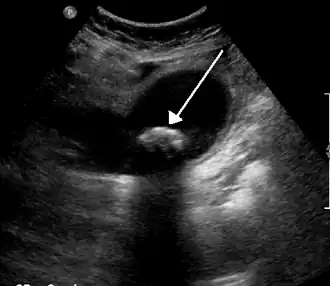

As cólicas biliares são em muitos casos a manifestação de cálculos na vesícula

Cólica biliar é a ocorrência de dor quando uma pedra na vesícula biliar bloqueia temporariamente o ducto cístico.[1] Na maior parte dos casos a dor situa-se na parte superior direita do abdómen, podendo irradiar para o ombro.[2] A dor dura geralmente de uma a algumas horas.[1] É frequente manifestar-se depois de uma refeição farta ou durante a noite.[1] São também comuns ataques sucessivos.[3]

A formação de cálculos biliares tem origem na precipitação de cristais que se agregam para formar pedras. Os cálculos mais comuns são constituídos por colesterol.[4] Entre outros possíveis constituintes estão cálcio, bilirrubina, pigmentos ou cálculos mistos.[4]Entre outras condições que produzem sintomas semelhantes estão a apendicite, úlcera péptica, pancreatite e a doença de refluxo gastroesofágico.[1]